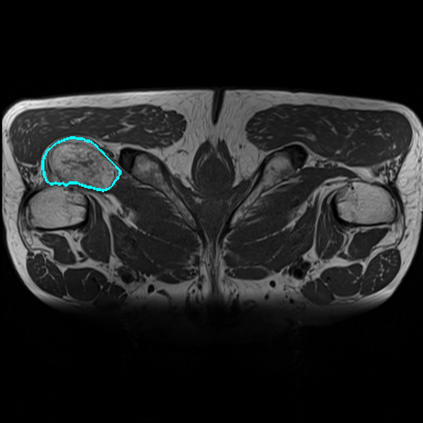

Radiomics uses quantitative medical imaging features to predict clinical outcomes. Currently, in a new clinical application, finding the optimal radiomics method out of the wide range of available options has to be done manually through a heuristic trial-and-error process. In this study we propose a framework for automatically optimizing the construction of radiomics workflows per application. To this end, we formulate radiomics as a modular workflow and include a large collection of common algorithms for each component. To optimize the workflow per application, we employ automated machine learning using a random search and ensembling. We evaluate our method in twelve different clinical applications, resulting in the following area under the curves: 1) liposarcoma (0.83); 2) desmoid-type fibromatosis (0.82); 3) primary liver tumors (0.80); 4) gastrointestinal stromal tumors (0.77); 5) colorectal liver metastases (0.61); 6) melanoma metastases (0.45); 7) hepatocellular carcinoma (0.75); 8) mesenteric fibrosis (0.80); 9) prostate cancer (0.72); 10) glioma (0.71); 11) Alzheimer's disease (0.87); and 12) head and neck cancer (0.84). We show that our framework has a competitive performance compared human experts, outperforms a radiomics baseline, and performs similar or superior to Bayesian optimization and more advanced ensemble approaches. Concluding, our method fully automatically optimizes the construction of radiomics workflows, thereby streamlining the search for radiomics biomarkers in new applications. To facilitate reproducibility and future research, we publicly release six datasets, the software implementation of our framework, and the code to reproduce this study.